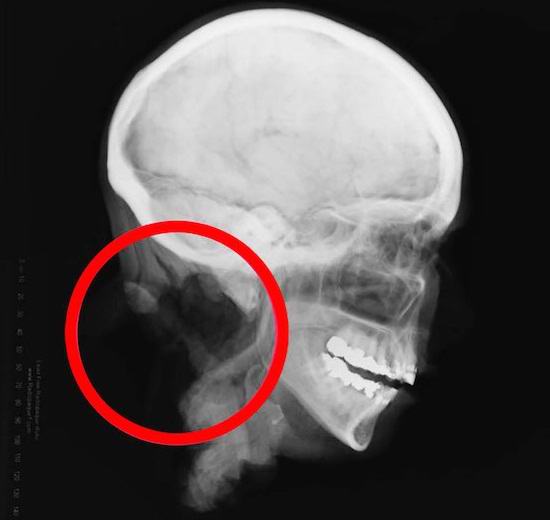

La sezione che separava la testa dal corpo (che non è stato ancora possibile trovare) era abile: estremamente regolare e preciso. Vertebre rimanenti ben rimosso dalla colonna cervicale. Ciò ha spinto gli investigatori a l’idea che un criminale con un professionista abilità chirurgiche. Non è stato possibile identificare la donna: in né il cast dei suoi denti, né l’analisi del DNA, né ritratti mediatici di Jane Dow.

Inoltre, ancora più interessante e peggio. Volevano esperti forensi esaminare gli occhi del defunto, ma furono sorpresi di scoprire che l’oftalmico non c’erano mele nel cranio. Invece, quelli rossi sono stati inseriti nelle orbite. palline di gomma con lenti sottili. Innanzitutto sono sorti gli specialisti versione che gli occhi sono stati rimossi per scopi di donatore, ma ha causato dubbi. Perché allora sostituire gli occhi con un tal “cosmetico protesi “? Sembrava quel misterioso criminale volevo mantenere questa testa come una mostra o una decorazione. I medici locali non hanno mai visto nulla di simile prima.

Gli esperti hanno esaminato queste teste imbalsamate e sono arrivati a Concludo che sembrano la testa di Jane Doe. In particolare, hanno così le vertebre cervicali furono rimosse magistralmente e quelle inserite erano presenti gli occhi. Tuttavia, quest’ultimo può essere spiegato come segue: occhi non imbalsamare bene, in modo che la testa appaia come vivere, abbiamo bisogno di bulbi oculari artificiali. Sfortunatamente per questi le due teste non hanno avuto la stessa indagine approfondita, tuttavia, tutto indicava che i nuovi reperti sono identici alla testa Jane Doe